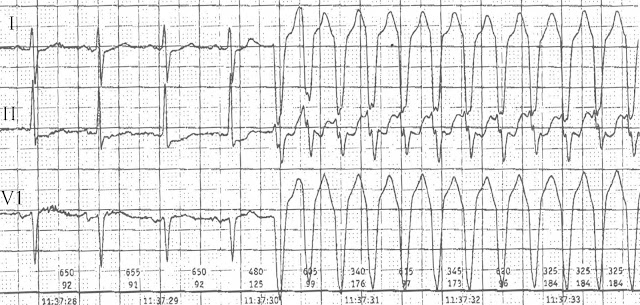

Další v nové sérii EKG video kazustik. Tentokrát se podíváme na matoucí záznam z EKG Holter monitorace, který nám přišel ke konzultaci a „zvážení dalšího postupu“ od ambulantního kardiologa.

Je na EKG supraventrikulární tachykardie s aberantním převodem na komory, nebo komorová tachykardie?